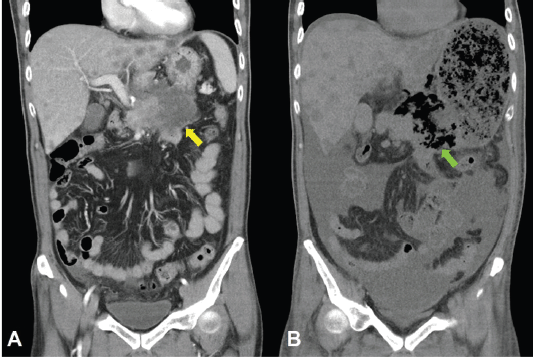

Unfortunately, a catastrophic event did happen 2 days after finishing the first course of chemotherapy. The patient experienced sudden onset of intolerable abdomen pain with hypoactive bowel sounds, muscle guarding, and definitely apparent rebounding pain. An emergent non-contrast CT scan gave a picture of distended stomach fully filled with foods, irregular mottled gas collections between stomach and duodenum, ascites accumulation, and free air in the abdomen cavity, leading to an impression of gastrointestinal tract perforation with the perforation site clearly seen (Figures 6–8). In comparison with CT scan performed at initial diagnosis, it seemed that a severe necrotising tumour lysis induced by chemotherapy, morphologically resembling emphysematous pancreatitis [14–16], could explain the whole scenario logically.

Figure 8. CT scan of the abdomen, coronal view. A. June 8, 2019. Yellow arrow: the huge gastric tumour. B. July 3, 2019. Green arrow: Necrotising tumour lysis simulating emphysematous pancreatitis.